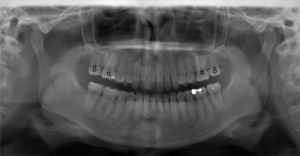

(治療後:写真右)

上顎左右ともに第二大臼歯(7)ではなく、第三大臼歯=親知らず(8)を咬み合わせに参加させ、安定した、咬合再構成を行いました。